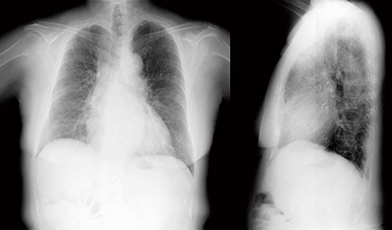

胸部単純X線写真では,下肺野優位に網状影,すりガラス状陰影が認められる。単純CT画像(図1)では,上肺野ほどの陰影はないが,下肺野には気管支血管側周囲から胸膜下にかけて網状影,すりガラス状陰影が認められ,膠原病肺が疑われる。胸部X線動態画像(図2)では,正常例と比べて下肺野および胸郭の幅の動きが悪い印象であった。また,胸部X線動態画像の呼気時から吸気時にかけての変位をベクトル表示した画像(図3)を見ると,当院の正常コントロール例と比較して下肺野の動きが悪い印象である。

図1 症例1:胸部単純CT画像